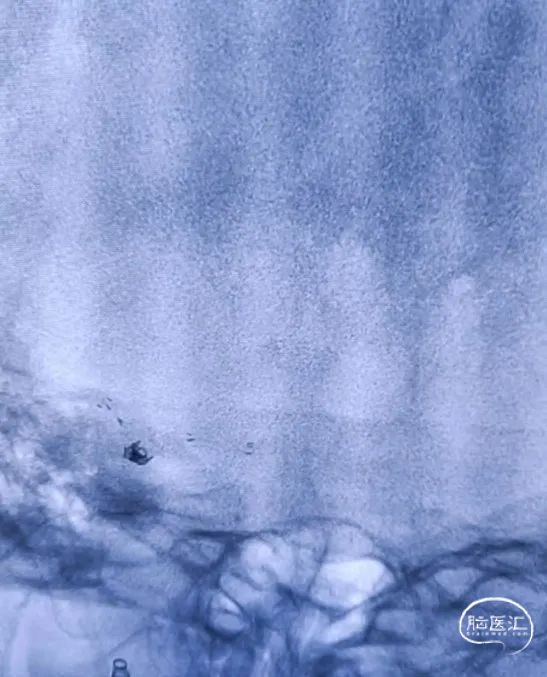

左侧颈内动脉迂曲,在SL-10微导管及Synchro微导丝配合下将6F Envoy输送至左侧岩骨段近端。

XT-17支架微导管和SL-10栓塞导管到位(如下视频)。

预填部分2mm*4cm Target弹簧圈进行成篮,然后将4.5*21mm Atlas支架到位并进行半释放,半释放支架后,继续填入2mm*4cm Target弹簧圈。

将Atlas支架全部释放(如左动态影像)

Target 2mm*4cm弹簧圈成篮满意,支架打开良好。

术后造影

术后造影(如下动态影像)。